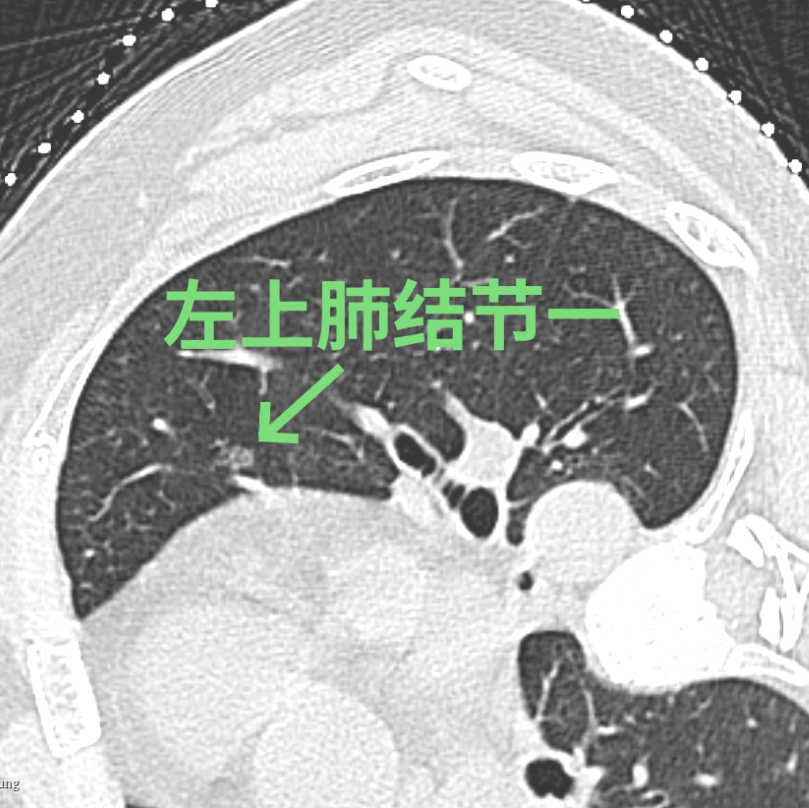

经过徐驯宇主任医师、黄郴副主任医师和王捷阳医师的反复讨论,决定为刘女士实施杂交手术:首先由黄郴和王捷阳在CT引导下为刘女士左上肺的小结节打上金属钩作为标记,然后再对左下肺较深的结节进行热消融治疗;接着由徐驯宇主刀为刘女士进行胸腔镜下左上肺结节的切除。在术中,徐驯宇按照之前在CT引导下置入的金属钩,很快就定位到左上肺的磨玻璃结节,并进行精准的局部切除,整个过程仅耗时30分钟。术后的病理报告显示,这3个结节分别为两个原位癌和一个非典型腺瘤样增生。经过量身定制的杂交手术,刘女士顺利解除了肺部的3个健康隐患,3天就顺利恢复出院。

▲术中结节变化